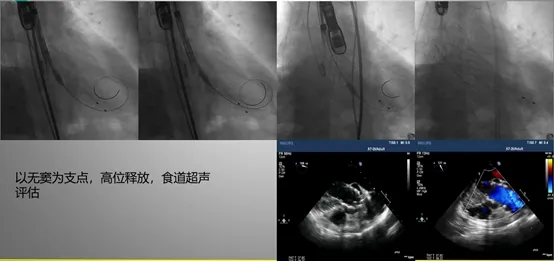

单纯主动脉瓣反流患者常因瓣环及左心室流出道扩张、瓣叶缺乏钙化锚定点,以及舒张期血流冲击力较大,术中易出现人工瓣膜锚定困难及移位风险。

针对这一问题,可考虑选用特定设计的人工瓣膜(如带有定位键的瓣膜),并综合运用STABLE技术原则、NCPI验证原则及“三明治法”等技术策略。其中,“三明治”技术需在术前详细评估主动脉窦部空间和冠脉开口高度,以避免影响冠状动脉血流,同时应确保置于窦底的第一个瓣膜位置准确,从而保障整体操作的安全性与有效性。

NCPI验证原则

三明治技术